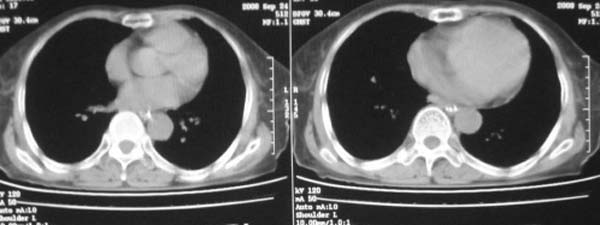

女,78岁,声嘶月余,否认有既往病史,有粉尘接触史10年。

尘肺合并肺癌。

肺癌伴纵膈、双颈部淋巴结转移;尘肺。

右上肺癌伴肺内转移及纵隔淋巴转移 左上肺结核 图像有点模糊

考虑肺癌伴纵膈、双颈部淋巴结转移;